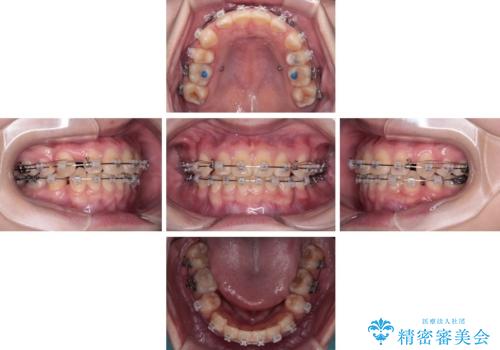

- 矯正装置

- クリアブラケット

そのため、限られた期間内に効率よく治療を完了するために、「抜歯スペースの確実な閉鎖」「深い噛み合わせ(過蓋咬合)の改善」の2点を主軸とした治療計画を立てました。

結果的に1年半で、再度転勤になる前に治療を終えることができました。